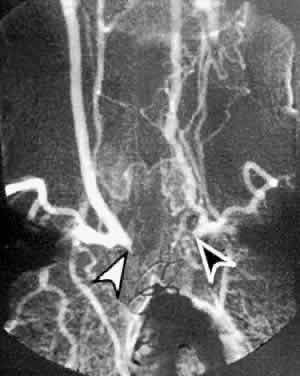

With the use of orbital color Doppler imaging, the central retinal and posterior ciliary artery peak systolic velocities have been reported to be markedly reduced in ocular ischemic syndrome, as would be expected (Fig. 8).13 Reversal of ophthalmic artery blood flow, which probably represents collateral blood flow to lower resistance vascular beds, was detected in 75% of eyes with ocular ischemic syndrome. It is interesting to note that although high-grade carotid stenosis, reversal of ophthalmic artery flow, and decreased central retinal artery flow have been associated with ocular ischemic syndrome, this combination in and of itself has not been sufficient to routinely produce decreased vision. Absence of detectable posterior ciliary arterial blood flow was the only reliable indicator of poor vision.

Fig. 8. Color Doppler imaging study of the central retinal artery in an eye with ocular ischemic syndrome (left). Areas in red superimposed on the B-scan image depict blood flow moving toward the transducer, mostly representing arterial flow. Areas in blue depict flow, mostly venous, away from the transducer. Notice the reduced systolic peaks of the time-velocity waveform (graph below the B-scan image) in contrast to the normal pattern of the uninvolved contralateral eye (right). (Ho AC, Lieb WE, Flaharty PM et al: Color Doppler imaging of the ocular ischemic syndrome. Ophthalmology 99:1453, 1992)